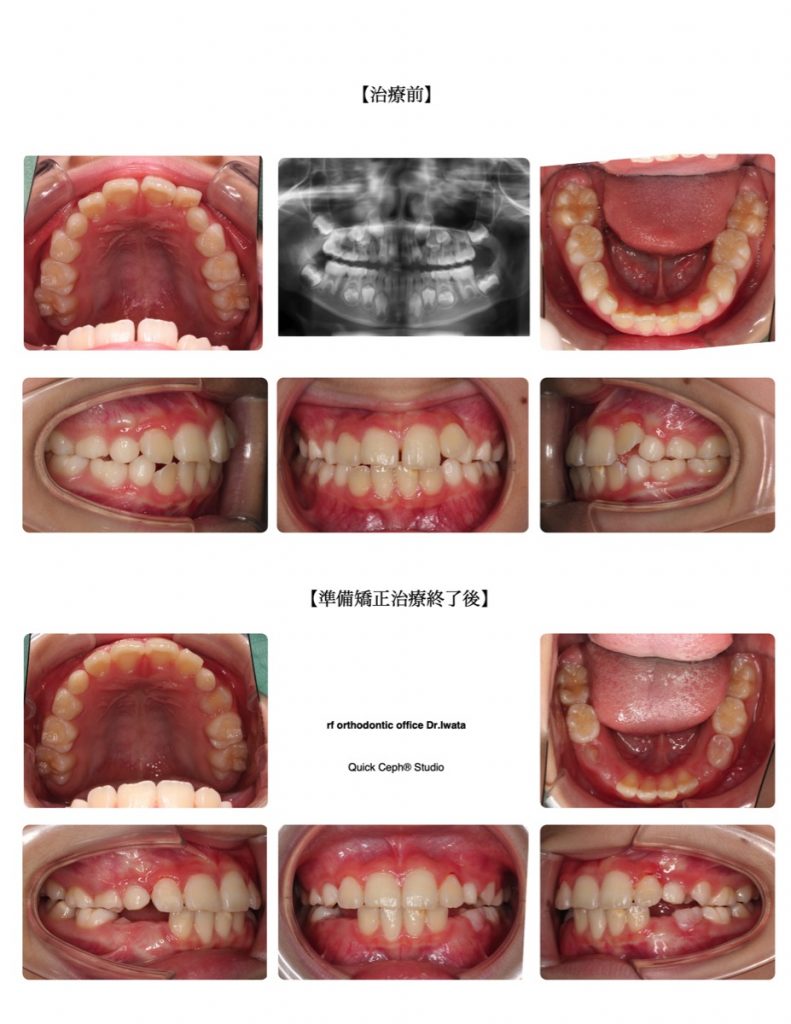

叢生症例 <正中離開を伴う上顎前歯叢生に対する準備矯正治療>

【主訴】大人の前歯が出始めたら窮屈な感じになり、重なって生えてきた。上の前歯の隙間も目立ってきたので一度綺麗にしたい。 【主な症状】叢生 正中離開 【矯正歯科治療のリスク・副作用】う蝕、歯肉炎、歯根吸収 ※矯正治療費には […]